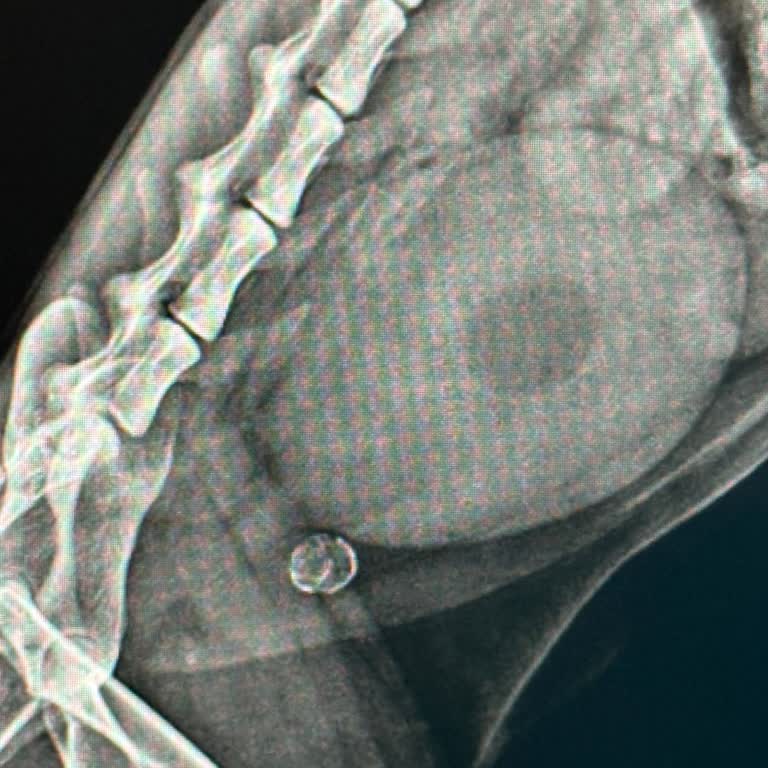

25.11.2025'de kedimi idrar yolu tıkanıklığı şikayetiyle Alanya Bellus Veteriner Kliniği’ne götürdüm. İlk başvurudan sonra kedim yaklaşık beş gün boyunca bu klinikte yatırılarak “işlem/tedavi” adı altında çeşitli müdahalelere maruz kaldı, ancak bu sürecin sonunda bana kesin, net ve açıklayıcı bir tan...